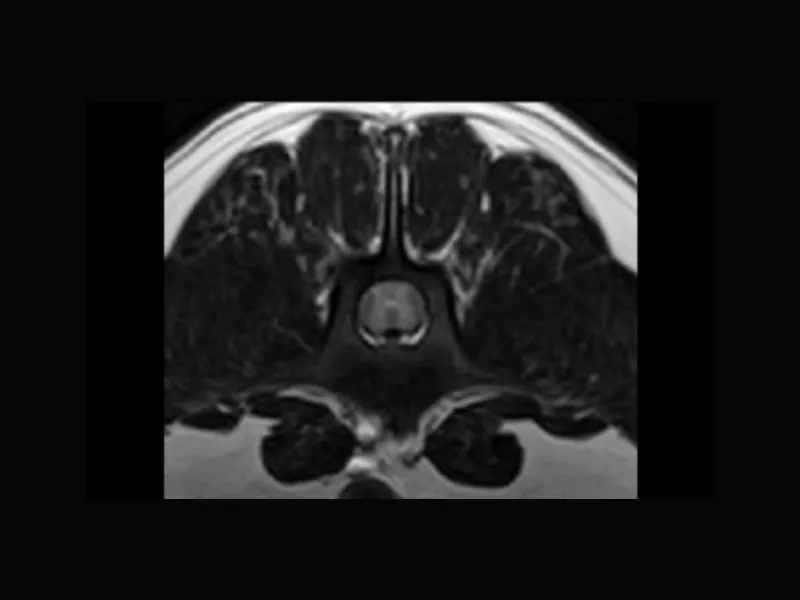

Supreme vet-mr – High resolution transverse T2W of a dog with spinal cord pathology